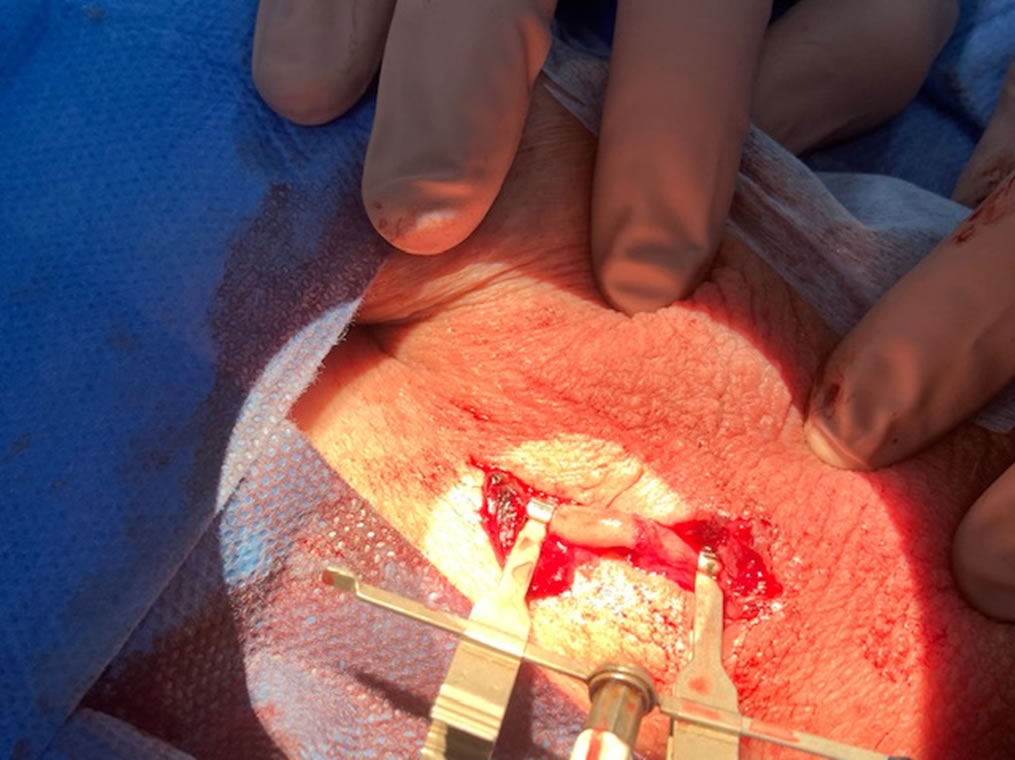

Técnicamente la llamamos vaso-vasostomía y consiste en unir (mediante microcirugía) los conductos deferentes seccionados durante la vasectomía. Esta unión o anastomosis permite que los espermatozoides vuelvan a pasar por el deferente y salir con el semen durante la eyaculación

Se trata de volver a unir lo que se separó en la vasectomía y que el hombre vuelva a ser fértil. Debe realizarse con microscopio operatorio.